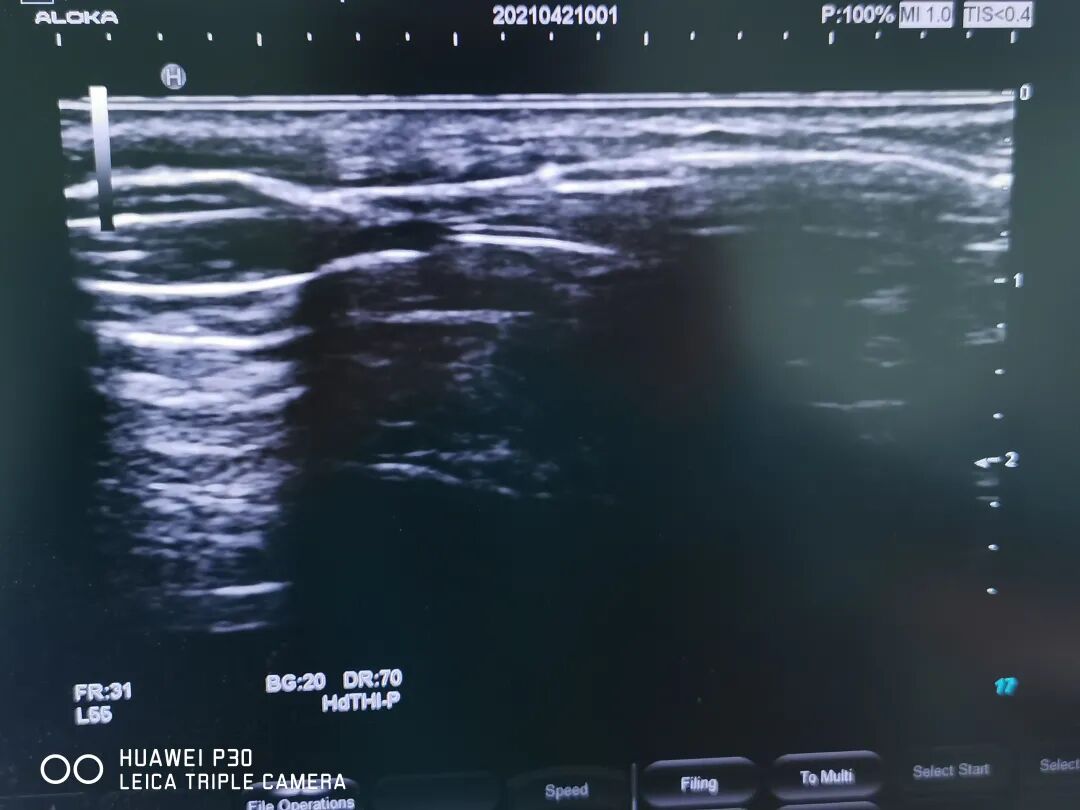

患者術(shù)中

▲術(shù)中球囊擴(kuò)張切記 ▲術(shù)中球囊全部張開